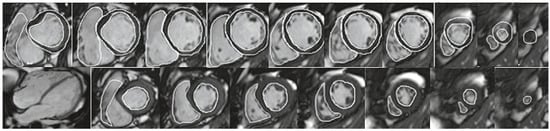

Acquisition: We recommend acquiring a short-axis stack of contiguous slices covering both ventricles from base to apex, with the first and last slices without ventricular mass to ensure a complete coverage of the ventricles (Figure 2a,b). For dilated and hypertrophied right ventricles, a separate stack oriented parallel to the tricuspid valve plane to assure optimal alignment should be considered. Additionally, a transaxial stack or long-axis stack can be considered in specific lesions. Details of cine imaging according to patient size are described in Table 1.

Figure 2.

(a) SSFP short axis cine stack with volumetry of both ventricles. Top: Tracings of the RV and LV endocardial borders and LV epicardial border. Bottom: SSFP end-diastolic still frame of 4-chamber view. Systolic tracings of the RV and LV endocardial borders. LV ejection fraction (EF) 61%, LV end-diastolic volume index (EDVi) 94 ml/m2, LV endsystolic volume index (ESVi) 37 ml/ m2, LV mass index 67 g/m2. RVEF 61%, RVEDVi 80 ml/m2, RVESVi 31 ml/m2. Patient with surgically repaired patent ductus arteriosus and correction of coronary anomaly (left anterior descending artery originating from MPA), mild aortic regurgitation. (b) Univentricular heart with situs inversus, mesocardia, unbalanced atrioventricular (AV) septal defect with common AV valve, right ventricular dominance, transposition and total cavopulmonary connection (TCPC). Top: SSFP long axis cine still frames and abdominal situs. Bottom: SSFP short axis cine stack with volumetry of both ventricles together: VEDVi 125 ml/m2, EF 42%.

Analysis: The use of dedicated software is recommended. Endo- and epicardial left and right ventricular borders are manually traced at end-diastole and end-systole. The papillary muscles are included in the blood pool. The interventricular septum is included in the left ventricular (LV) mass. Practice varies regarding whether the right ventricular (RV) trabeculations are excluded from or included in the blood pool. However, higher reproducibility has been reported for segmentation along the compacted myocardium and inclusion of trabeculations in the blood pool [23]. In the case of bundle-branch block, the end-diastolic and end-systolic phases of the right and left ventricles may occur at different times; thus the phase with the largest/smallest ventricular volume has to be evaluated for each ventricle independently. The RV outflow tract (OT) should be considered part of the right ventricle, even in cases with aneurysmatic dilatation such as in patients with repaired tetralogy of Fallot. Contour data for volumetric analysis should be stored in a database and remain available for comparison at the time of a subsequent examination [1,2].